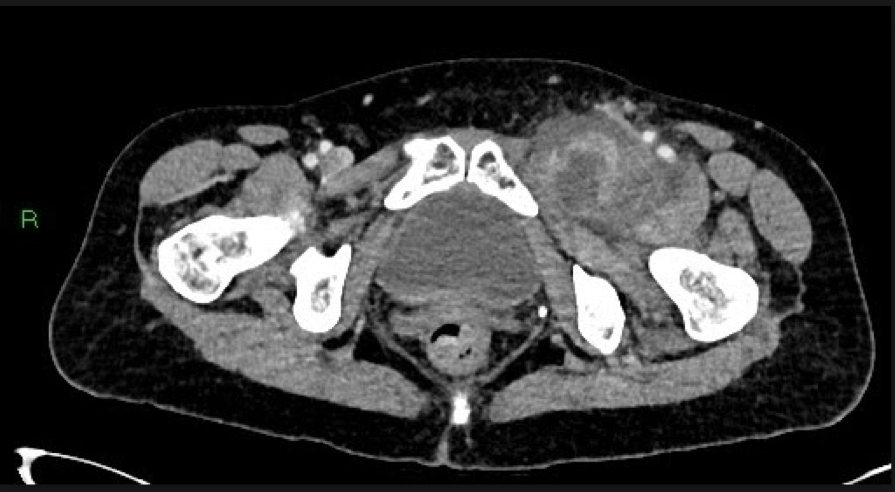

Fig.05. Contrast-enhanced portal-venous phase axial CT of the abdomen and pelvis imaging demonstrates a heterogenous, peripherally-enhancing, mixed density lesion with adjacent inflammatory fat stranding and lateral displacement of the femoral vessels.